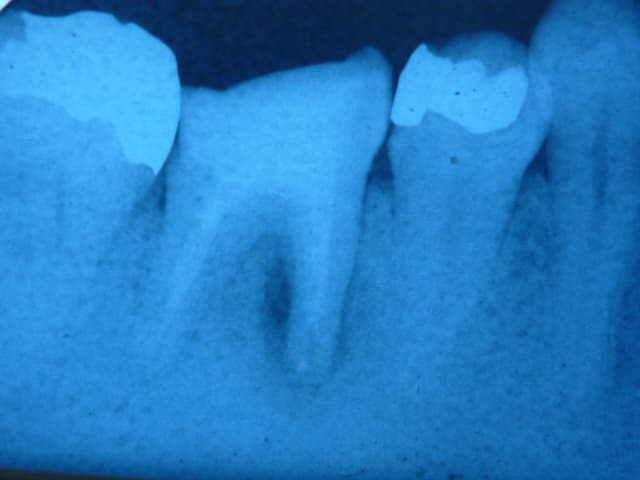

できるだけ歯を残すために—当院の症例紹介

当院では、可能な限り歯を残す治療を行っています。

こちらの患者さんは、他医院で「抜歯が必要」と説明を受け、当院へ来院されました。

診断の結果、私も抜歯の可能性が高いと判断しましたが、患者さんと相談し、

抜歯の可能性を理解いただいた上で、保存を目指した治療を開始しました。

症例写真1:術前

症例写真2:術後6ヶ月

この患者さんは、最終的に歯を残すことができました。状態によっては自費治療の高度な技術が必要となるケースもあります。